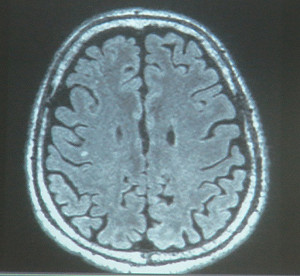

公布扁MRI 陳順勝:修護神經髓鞘可治癒

北榮:扁治療具急迫性 宜儘速轉院治療